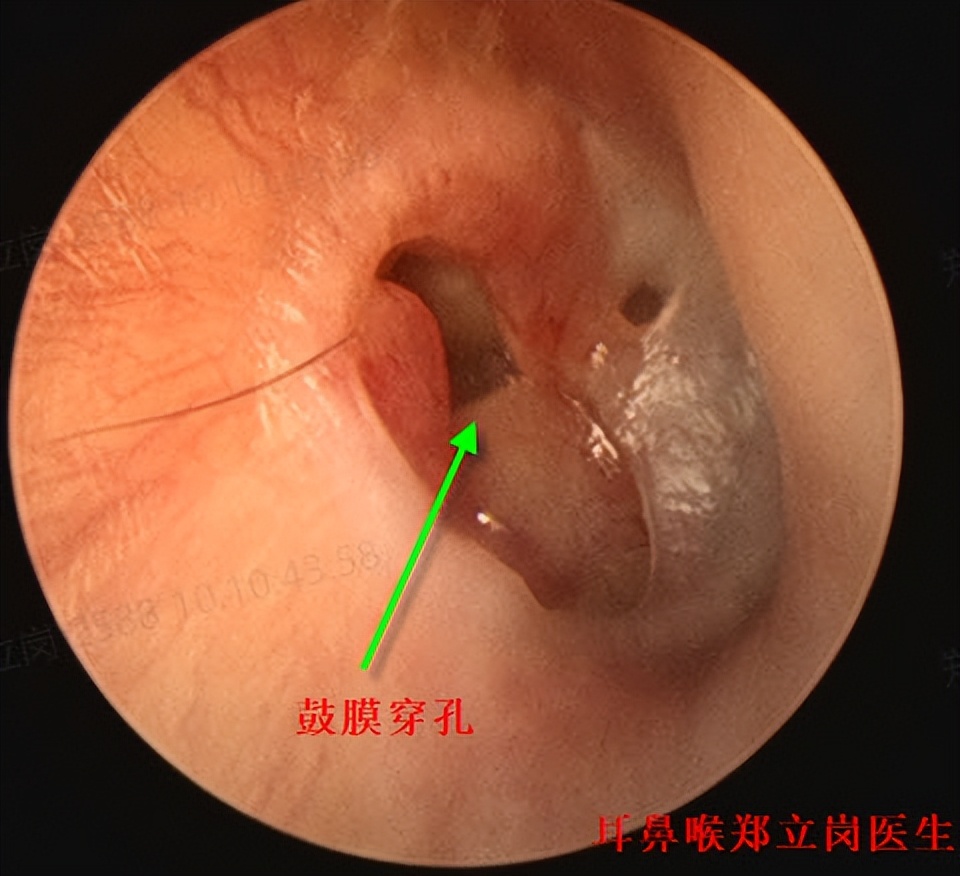

患者黄,女,62岁,广西南宁青秀人。患者右侧鼓膜大穿孔,鼓室中有肉芽组织,这次是专门从广西过来做耳内镜中耳炎微创手术的。

插管全麻后就开始了手术,在耳内镜下不用做任何的体表切口,直接翻起外耳道鼓膜皮瓣,可见鼓室中两个肉芽,予以清理后听骨链是完整的,活动可。取合适大小的耳屏软骨修剪后修补鼓膜,鼓膜修补好后检查了两遍确认没问题后就结束了手术。整个手术用时约50分钟,非常的顺利。术后查房患者无明显的不适,无手术相关的并发症。